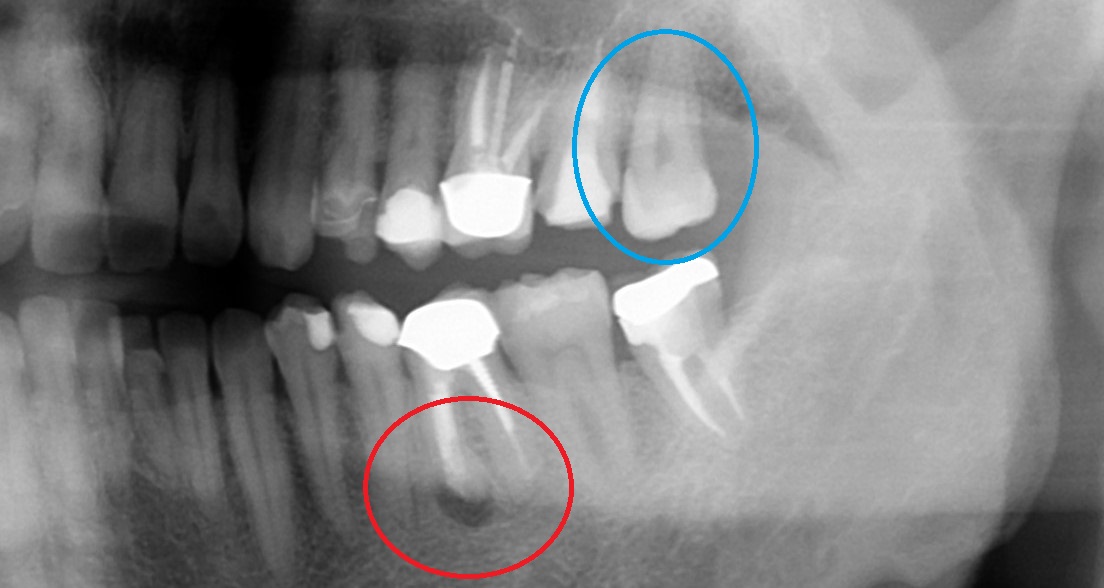

• Before

After

「歯を抜かないといけない」と言われたが、当院で抜かずに終えました。